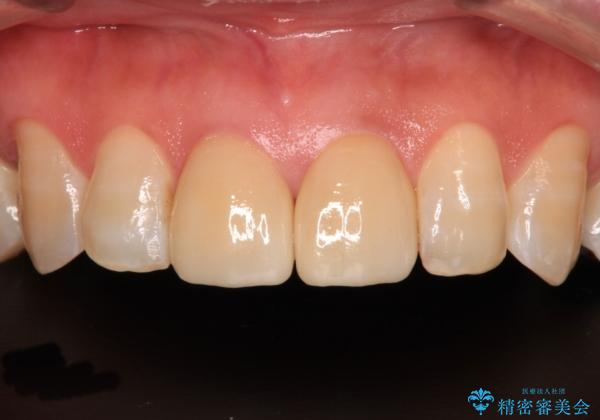

統一感のあるきれいな色調となり、患者様には大変満足していただきました。

グレーの色が透けて見える気がする点が気になっていらっしゃり、やや黄色みのある色を希望されていました。

仮歯に置き換えた後にオールセラミッククラウンにて補綴治療を行うこととしました。